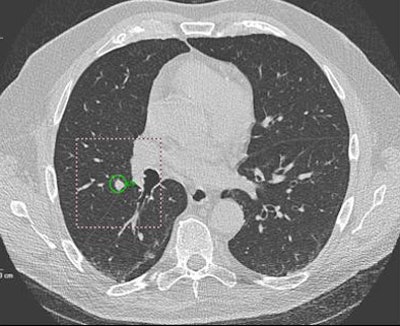

| Oblong nodule of 9 mm in left upper lobe was a true-positive CAD finding. |